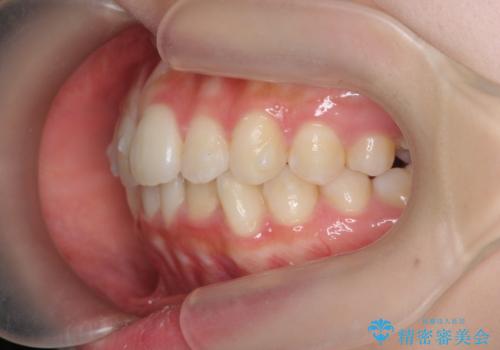

インビザラインライトで行う短期マウスピース矯正治療

- 前歯のガタつきを並べたいたいと、矯正治療を希望され来院されました。

とにかく短期間で前歯だけの治療を行いという希望が強く、全体矯正と前歯だけの部分矯正の仕上がりのイメージを確認したのち14枚のマウスピースで前歯のみの矯正治療を行っていくこととしました。

インビザラインライトは軽度なガタつきや傾斜の改善に用いられる全14枚のマウスピース矯正です。